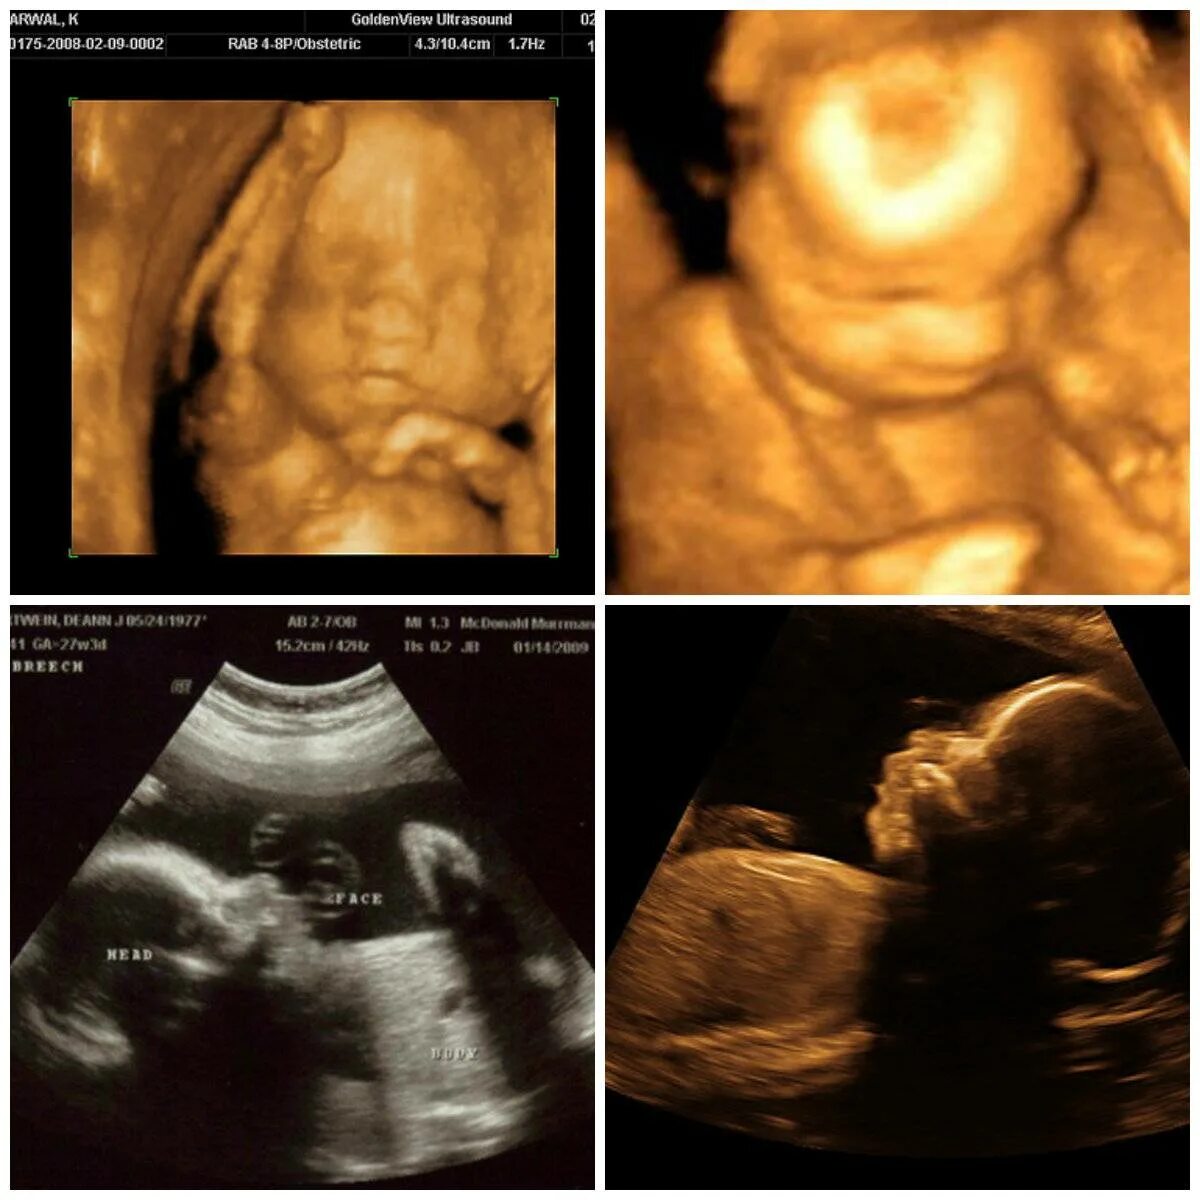

25 недель 2 дня